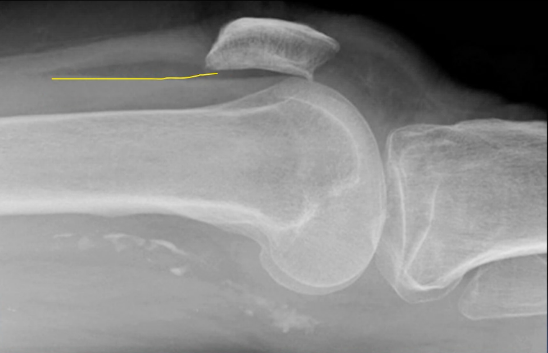

A 30 year old man presented to the ED with left knee pain after a cycling accident.

On examination there was no deformity, but it was painful for him to weight-bear. Movements of his knee were painful, and this limited his movements.

What is a lipohemarthrosis?

Results from an intra-articular fracture with escape of fat and blood from the bone marrow into the joint, and is most frequently seen in the knee.